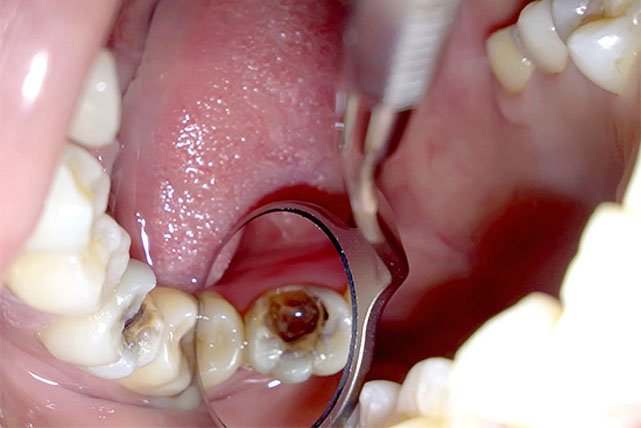

Це процедуру, що в стоматологічному світі називають ендодонтією. Ну, або просто — депульпація. Вона полягає в ліквідації пульпи — того самого нерва. Просто уявіть собі пучок нервів і кровоносних судин, які “живлять” зуб, як зайві дроти в ідеальній конструкції. Але коли цей пучок починає бунтувати, запалюватися — виникає потреба в його видаленні.

- Інфекція. Зуб гниє, пульпа гниє, гірше ніж зіпсоване м’ясо в холодильнику.

- Карієс — той ворог, що вразив зуб до мозку кісток (буквально).